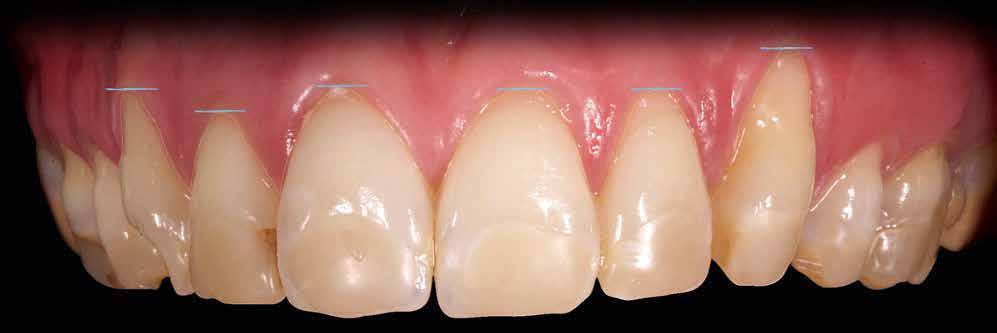

A cikkben egy fiatal nő kezelésének interdiszciplináris megközelítését foglaltuk össze, aki fogászati állapota miatt hoszszú ideje szenvedett fizikálisan és pszichésen is (1. ábra)

1. a–c ábrák: Kiindulási helyzet: fiatal páciens komoly fizikai és pszichés szenvedéssel.

Dr. Miguel Stanley, dr. Ana Gomes Paz, dr. Inês Miguel (Portugália) Dr. Christian Coachman (Brazília) 1. ábra: Kiindulási állapot (frontális irányból). 2. ábra: A kiindulási állapotról okkluzális irányból készített felvétel (felső állcsont). 3. ábra: A kiindulási állapotról okkluzális irányból készített felvétel (alsó állcsont). 4. ábra: A kiindulási állapotról készült panorámaröntgen felvétel (2015).